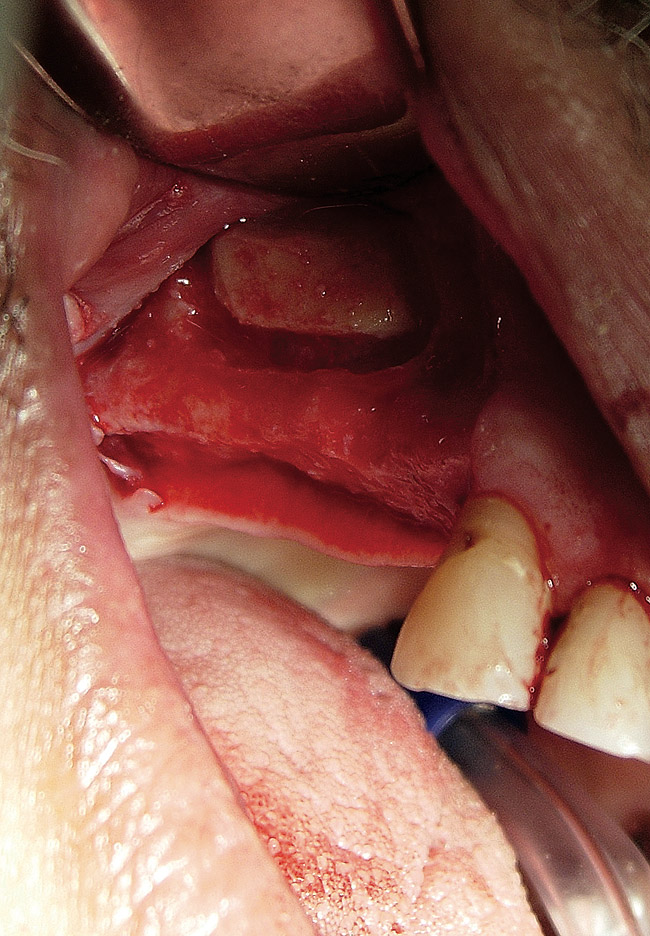

The lateral approach is also used for sinus floor elevation. It is indicated when there is reduced residual bone height, which does not allow standard implant placement or placement of implants in combination with minor sinus floor elevation using the osteotome technique (Figure 1, Figure 2 and Figure 3). Contraindications are excessive interarch distance due to unfavorable crown-to-root ratio, acute or chronic unresolved sinusitis, current sinus pathology (eg, cysts or tumors), lodged root tips in the sinus, history of heavy smoking, a systemic compromise, and psychological problems.

Figure  2  Outline of the lateral window

Figure 2